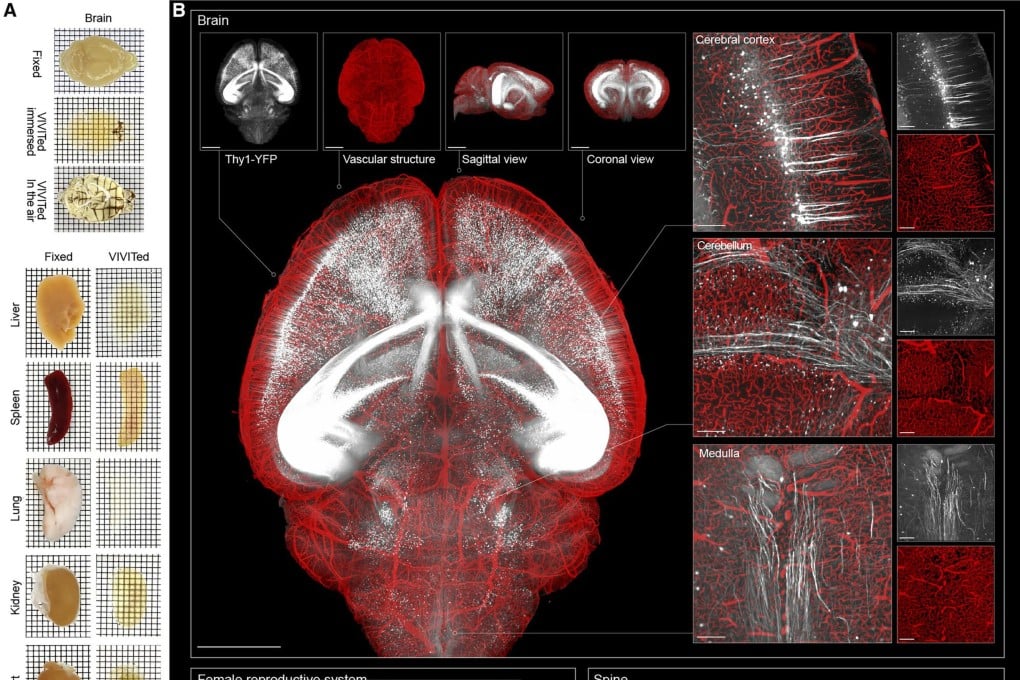

دانشمندان چینی موفق به توسعه تکنیک جدیدی شده‌اند که باعث شفاف‌سازی اندام‌ها شده و در عین حال، ساختار آن‌ها را حفظ می‌کند. این تکنیک می‌تواند در آینده برای ایجاد تصاویر بسیار دقیق و واضح مورد استفاده قرار بگیرد. در این بخش خبری از گجت نیوز با ما همراه باشید.

تکنیک جدید کشف شده از سوی دانشمندان چینی ممکن است کمک بسیار خوبی برای مشاهده درون کل اندام‌ها بدون نیاز به تشریح آن‌ها باشد.

این تیم تحقیقاتی در مقاله منتشرشده اظهار داشتند روش موردنظر با سایر شیوه‌های شفاف‌سازی، علی‌الخصوص در طول موج‌های کوتاه‌تر، بالاترین شفافیت را در طول موج‌های مختلف ایجاد می‌کند.

این مایع توانایی ورود به اندام را داشته و آن‌ها را به چیزی تبدیل می‌کند که حالت شیشه‌ای یونی نامیده می‌شود. در این حالت بافت شفاف شده و شکل اصلی یا ساختار ظریف خود را حفظ می‌کند، چرا که خبری از منبسط یا منقبض شدن نیست.

مایع‌های یونی هنگام خنک شدن، کریستال تشکیل نخواهند داد و این اجازه را می‌دهد بافت‌های درمان شده برای مدت طولانی در انبار سرد هم نگه‌داری شود. این فرایند رنگ‌های فلورسنت را به میزان زیادی افزایش داده و موجب می‌شود ۲ تا ۳۰ برابر روشن‌تر باشند.

هم اکنون به لطف تکنیک جدید کشف شده، سیگنال‌های ضعیف مانند پروتئین‌های نادر یا اتصال‌های ظریف نورونی هم قابل مشاهده هستند.

این تکنیک می‌تواند پیامدهای عظیم برای کاربردهایی مانند تصویربرداری سه‌بعدی داشته باشد و محققان را قادر خواهد ساخت با دقت بیشتری از کل اندام‌ها در مقیاس میکروسکوپی نقشه‌برداری کنند.

در تئوری می‌توان گفت تکنیک موردنظر در طیف وسیعی از اندام‌ها مانند مغز، طحال و هر چیزی در میان آن‌ها استفاده می‌شود.